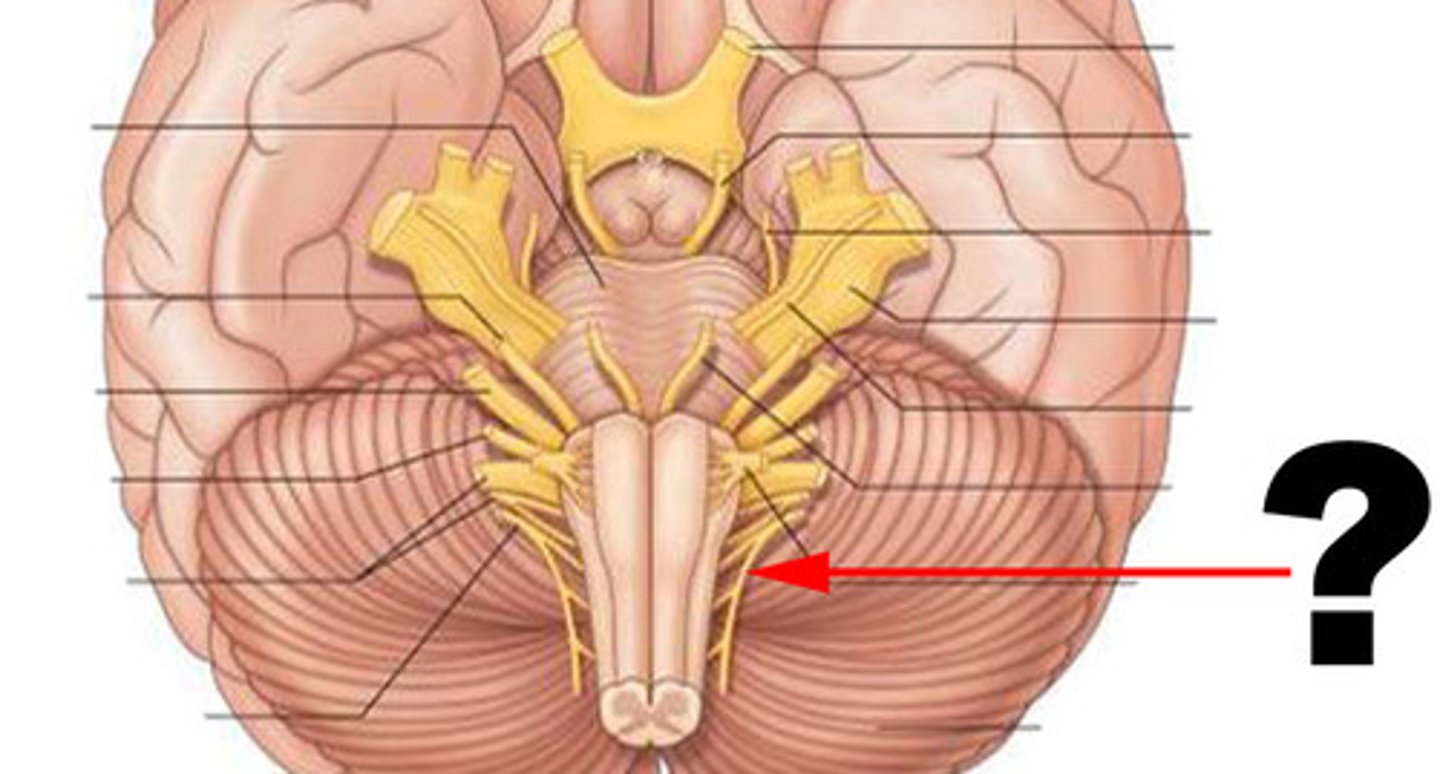

medulla oblongata

most inferior part of the brain stem; regulates breathing, heart rate, & blood pressure

the 'olives'

oval-shaped structures located on the anterior surface of the medulla, lateral to the pyramids

vestibulocochlear nerve

receives sensory input & sends motor output to cochlea of the inner ear for hearing

glossopharyngeal nerve

relays sensory & motor impulses related to taste, swallowing & deglutition

vagus nerves

processes input/output of pharynx, larynx & thoracic/abdominal viscera

accessory nerves

controls swallowing via vagus nerves

hypoglossal nerves

controls tongue movement; speech

pons

center structure of the brain stem, located between the midbrain and the medulla oblongata

trigeminal nerves

regulates sensory input from head & face, governs chewing

abducens nerves

controls eyeball movement, particularly abduction (outward gaze)

facial nerves

regulates facial movements, saliva, tears

vestibulocochlear nerves

the vestibular and cochlear nuclei in the pons are involved in balancing and hearing

midbrain

or mesencephalon extends from pons to diencephalon. the pons is the center structure of the brain stem, located between the midbrain and the medulla oblongata

cerebral peduncles

located on the ventral surface of midbrain. has corticospinal tract (voluntary movements) & corticobulbar tracts (motor control of face & head)